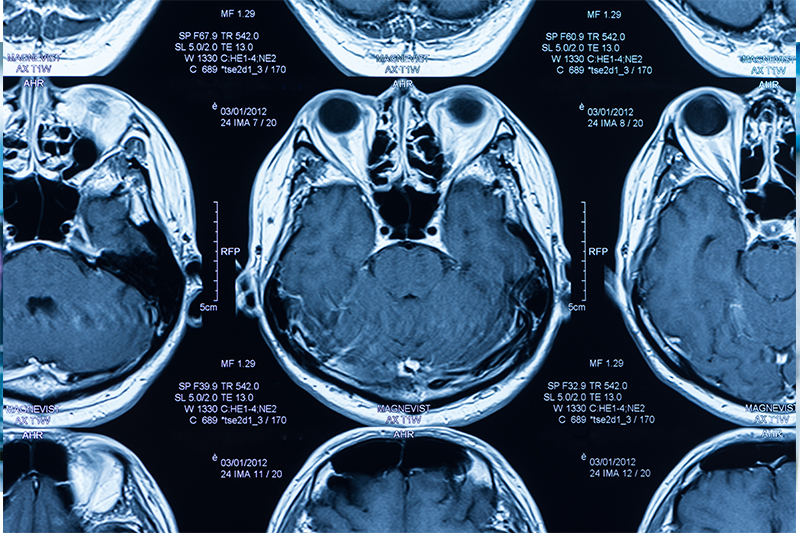

MRI 核磁共振成像(磁力共振,Nuclear Magnetic Resonance Imaging)

MRI技術主要是利用水分氫原子核,達到成像效果。原理是將病人置於磁場之中,並用電磁波照射,以達到氫原子並振的效果,再分析其回饋的電磁波,從而繪製影像。

MRI應用層面廣泛,在某些情況下亦比CT或X光優勝,特別是在軟組織的成像相當清晰,這是由於MRI大多利用水分的氫原子核作為成像元素,因此在軟組織的成像效果較為出色。一般在心血管或腦血管疾病、腫瘤的情況,MRI都是較好的檢查選擇。不過對於肺部、肝臟、胰腺等部分器官的檢查效果就不及X光或CT。因此檢查工具的選擇仍需視乎情況而定。

相較X光與CT,MRI所帶來的損傷較低,原因一是MRI不含輻射;原因二是MRI不需使用顯影劑。而使用MRI的危險性則包括機器會產生持續的噪音、器官溫度會升高,另外檢查房間內是不可以出現任何金屬,包括病人體內的心臟起搏器,否則將會被強大的磁力吸過去,造成危險。但總括而言,MRI仍是相當安全的檢查工具。